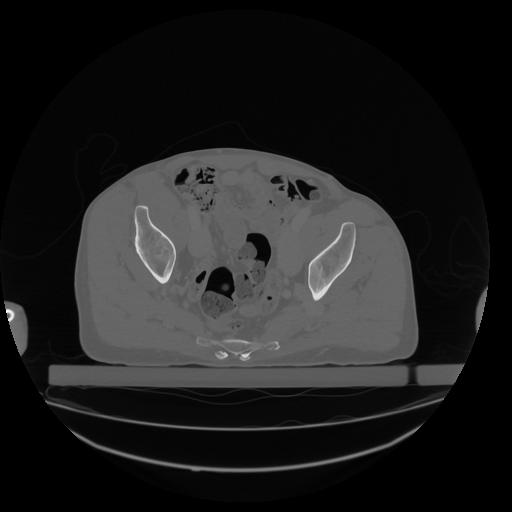

34 CUERPO,CE,Vol,1.0,CUERPO,,